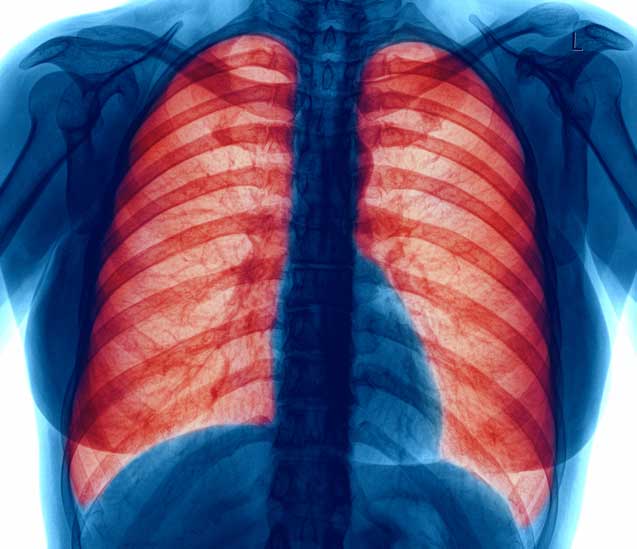

Chronic obstructive pulmonary disease, or COPD, is becoming increasingly more common. It is caused by damage to the lung tissue due to inhaled toxins, like cigarette smoke. It can become so severe that lung surgery or a lung transplant may become a patient’s only option at a full life. Stem cell therapy is now being explored as a potential therapy for patients suffering from COPD symptoms.

Chronic obstructive pulmonary disease, commonly referred to as COPD, is a group of progressive lung diseases. The most common are emphysema and chronic bronchitis. Many people with COPD have both of these conditions. Emphysema slowly destroys air sacs in your lungs, which interferes with outward airflow. Bronchitis causes inflammation and narrowing of the bronchial tubes, which allows mucus to build up. Chronic bronchitis, emphysema, asthma, and infectious diseases can contribute to the development of chronic obstructive pulmonary disease. The primary cause of chronic obstructive pulmonary disease is cigarette smoking and exposure to tobacco smoke. Other causes include air pollution, infectious diseases, and genetic conditions. Smoking tobacco, secondhand smoke, air pollution, alpha-1 antitrypsin deficiency, and a few other conditions increase the risk factors of COPD. The stages of chronic obstructive pulmonary disease range from stage 1 to stage 4. As the stage number increases, the disease and its symptoms will progressively become worse. Stage 4 is also known as “end-stage” chronic obstructive pulmonary disease because it is the final stage before death. To diagnosis COPD, the doctor will take the patients breathing history and any exposure to irritants such as cigarette smoking or other agents.

There’s no cure for COPD, but treatment can help ease symptoms, lower the chance of complications, and generally improve quality of life. Medications, supplemental oxygen therapy, and surgery are some forms of treatment. Treatments can also include avoiding any of the risks or causes of COPD like cigarette smoke or toxic fumes, or in a small number of patients, lung surgery or lung transplant. COPD makes it harder to breathe. Symptoms may be mild at first, beginning with intermittent coughing and shortness of breath. As it progresses, symptoms can become more constant to where it can become increasingly difficult to breathe. You may experience wheezing and tightness in the chest or have excess sputum production. Some people with COPD have acute exacerbations, which are flare-ups of severe symptoms.